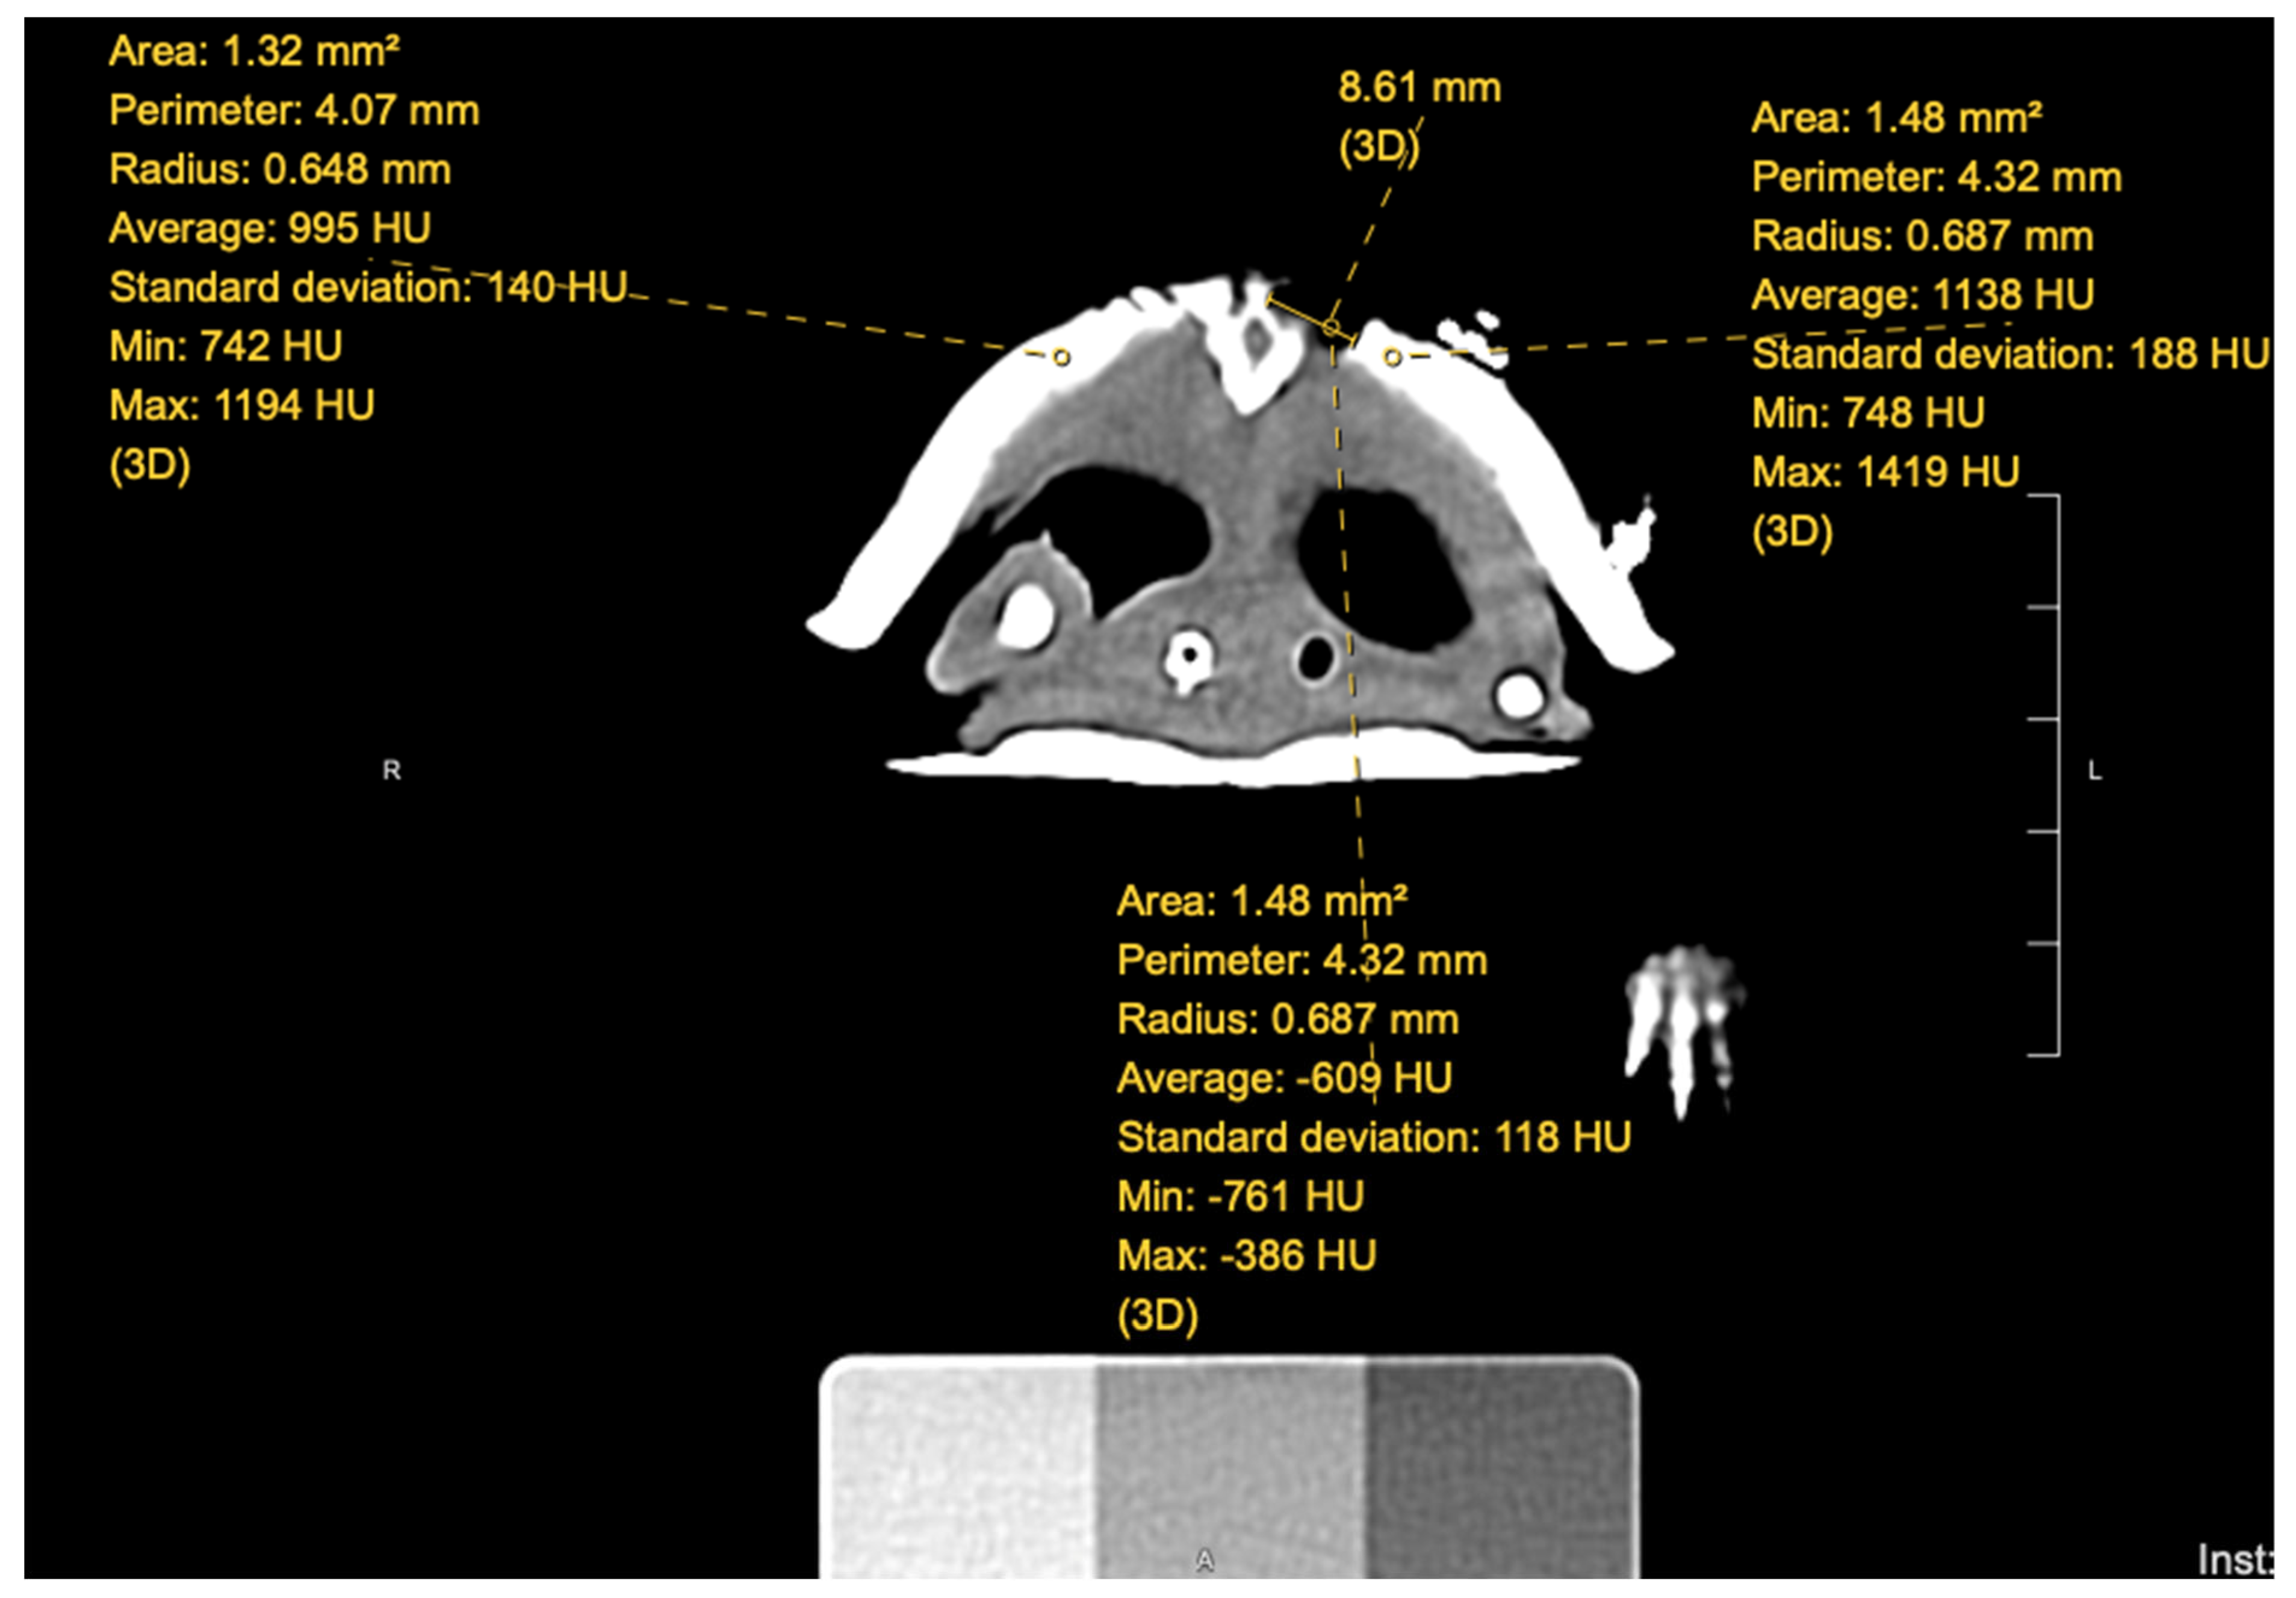

An individual (AS) blinded to the groups in which each turtle was placed evaluated the CT scans that were performed at each timepoint. Using Hounsfield units, a quantitative measurement for radiodensity, the blinded individual took measurements within the fracture site at the proximal, middle, and distal aspects for a single CT slice; for an example, see Figure 2. In addition, measurements of normal shell were also taken to the left and right of the fracture site. The measurements for normal shell were then averaged at each site, creating two sets of data for each fracture site: abnormal (fracture) and normal (shell). Each turtle, once the measurements were completed, had six sets of data for each CT scan.

Figure 2. Measurements of the turtle’s fracture site on a single CT slice. Hounsfield units of both fracture and normal shell along with the measurement of the width of the fracture.

Another limitation of this study was that the fracture site evaluated by the blinded individual was 1) not always the same diameter for the Hounsfield unit measurement and 2) not necessarily in the exact same spot on every scan (pre-, mid-, and post-treatment CT scans) between individual scans. Although the diameter measured for Hounsfield units was measured as relatively the same across the individual scans, between individuals, this diameter could be anywhere between 1.17 mm2 to 2.16 mm2, about a 1 mm2 difference. In addition, exact placement of measurements was determined by acknowledging the anatomy of the previously measured CT slice and finding the relatively same area within the next scan. Even though the measurements were as close as possible to the exact same site based on anatomy, this study cannot guarantee that each fracture was measured at the exact same location for every scan. Future studies should consider markers along the shell at the areas of measurement, as oftentimes, the hardware used to repair the turtle was used to help the blinded individual evaluate similar CT slices across scans.